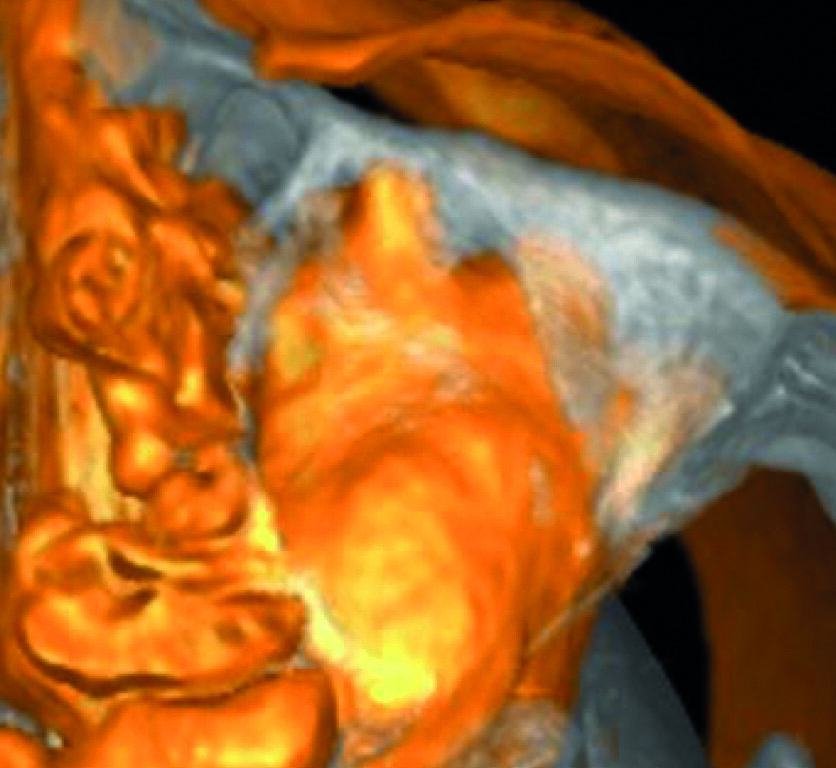

Un patient avait été adressé au cabinet en raison de problèmes associés à la fracture d’une lime. Il était pilote de ligne et se plaignait d’écoulements nasaux purulents lorsqu’il était en vol. La radiographie pré-opératoire (Fig. 1) a distinctement montré la présence de deux fragments d’une lime fracturée dans les canaux mésiaux et d’un cône traversant l’apex de la racine palatine. Après l’imagerie CBCT avec iCAT, il est apparu clairement que le sinus gauche était presque totalement rempli de liquide inflammatoire (Fig. 2) et que le cône présent dans le canal palatin pénétrait dans le sinus. Sur l’image de reconstruction multi planaire (MPR), nous pouvions également distinguer les deux fragments de lime fracturée dans les deux canaux mésiaux (Figs. 3 et 4) et aussi un autre fragment dans le sinus sans aucun contact avec le canal (Fig. 5). L’utilisation de différents filtres nous a permis de visualiser les fragments de lime (Figs. 6–9), ainsi que l’inflammation et le fragment de lime fracturée à l’intérieur du sinus. Nous avons également mieux perçu la position du cône qui émergeait du canal palatin et pénétrait dans le sinus.

Le plan de traitement a consisté à tenter de résoudre le problème par une approche classique et, au besoin, par une microchirurgie, en vue de conserver la dent. J’ai pu retirer le cône de la racine palatine a l’aide de limes H (Hedstrom) mais il était impossible de contourner les fragments de lime présents dans la racine mésiale, ou même de les atteindre avec des inserts ultrasoniques. Je me suis résolu à ne pas en faire trop afin de ne pas créer un nouveau problème, tel qu’une perforation de la paroi canalaire, et j’ai décidé de sceller les canaux (Fig. 10). La décision de traiter les canaux mésiaux par une approche chirurgicale a été prise immédiatement. J’ai sectionné 3 mm de la racine mésiale à l’aide d’une pièce à main Impact Air (SybronEndo), ce qui m’a donné une vue directe sur la membrane de Schneider, de laquelle le troisième fragment dépassait à peine (Figs. 11 et12). Je suis parvenu a le saisir délicatement et à l’extraire (Fig. 13). La figure 14 montre la situation post-opératoire, après la fin de la préparation à retro des canaux mésiaux.